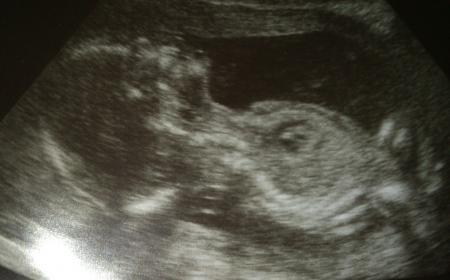

Und noch eins

Ja, eindeutiger geht es kaum! Herzlichen Glückwunsch zum kleinen Jungen!

Schön, dass alles prima ist! Und Glückwunsch zum Jungen...süsses Photo, wo man wirklich nicht übersehen kann!